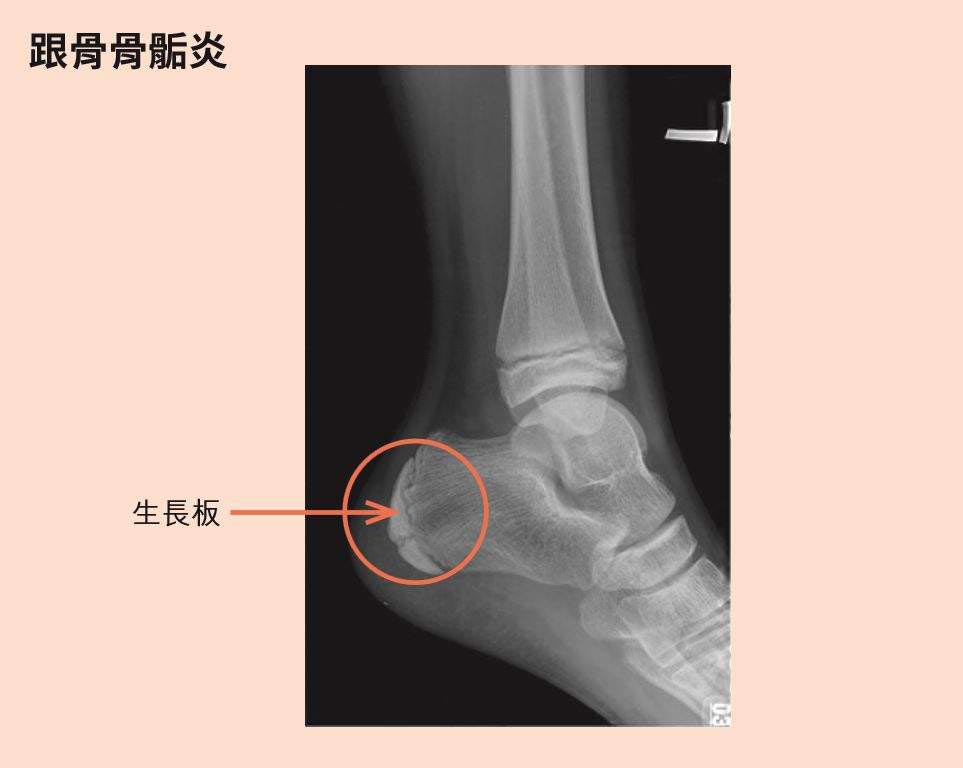

在發育期間,除了要注意小朋友能否長高外,也千萬不要忽略了「莫名其妙腳痛」的現象;眼鏡小醫朱家宏就提到,如果你家小朋友老是抱怨腳跟痛,很有可能是「骨骺炎」所致。骨骺炎不只發生在跟骨。基本上,只要有生長板的地方,就有可能會因為使用過當引起骨骺炎,但腳跟因為是運動、活動時應力最大的地方,所以也最容易發生跟骨骨骺炎(見下圖)。

再者,做做腳跟肌腱的牽引運動(stretch),將腳跟腱拉軟一點,與足底筋膜炎的牽引運動很類似,目的就是不要讓腳跟那麼緊,對腳底撞擊力就會下降。最後,就是家長應該具備正確認知。一旦小朋友發生了莫名其妙的腳跟痛,要了解,它非常有可能是骨骺炎而不是足底筋膜炎,但也有可能是腫瘤,甚至是肌腱斷裂、感染等等,雖然後者情況非常罕見。若要排除這些情形,找出正確原因,就應該要尋求專業醫生協助,照X光來確認。不要再相信一些錯誤的觀念,如「生長痛」、「轉大人」、「轉骨方」等等,或者在情況還不明瞭的時候,就跑去找國術館、民俗療法「喬一喬」,這樣只會讓病況越來越糟,花錢、耗時,又不濟事。